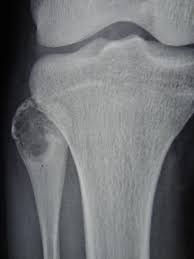

A chondroblastoma is a rare type of noncancerous bone tumor that begins in cartilage. This is the tough, rubbery connective tissue from which most bones develop. It plays an important role in the growth process. There are many different types of cartilage in the body. Chondroblastoma most often affects the ends of the long bones, near the growth plate, in the arms at the shoulder, and in the legs at the hip and knee. It is also called Codman’s tumor. Chondroblastoma can affect people of all ages. But, it’s most common in children and young adults. It’s also more common in males than females.